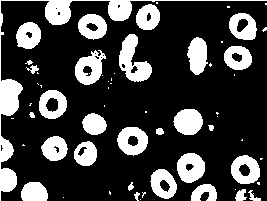

The output of this step is a binarized image, from which the areas corresponding to isolated cells or a cluster of cells, together with their contours, can easily be extracted. Before the extraction of cells or clusters of cells, the small objects that may interfere with the classification are removed. In addition, all detected areas that touch the border of the image are eliminated and are not taken into account in the following steps of the method. In general, it is very difficult to classify an object that is on the border of an image, only a part of which is visible. Some examples are displayed in Figure 2, where we show the original image and its segmentation obtained using the method previously described.

Refer to caption

(a)

(b)

(c)

(d)

Figure 2: (a) Original input image. (b) Result of Chan-Vese segmentation for image (a). (c) Original input image. (d) Result of Chan-Vese segmentation for image (c).